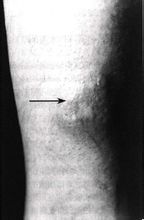

皮損最常見於脛前區,開始可為一側,隨後擴展累及兩小腿伸側,多呈對稱性分布少數亦可見於手、臂及面部,偶見於軀幹部。損害為圓、長圓或不規則圓形,腫脹堅實,加壓無凹陷的斑塊邊界清楚。呈蠟樣半透明至玫瑰或淡紅色,有時可帶有棕或棕黑色。表面凹凸不平。毛孔粗大可為橘皮狀健康搜尋。局部常有出汗增多及毳毛旺盛粗黑有光。自我感覺可伴瘙癢或蟻行感。